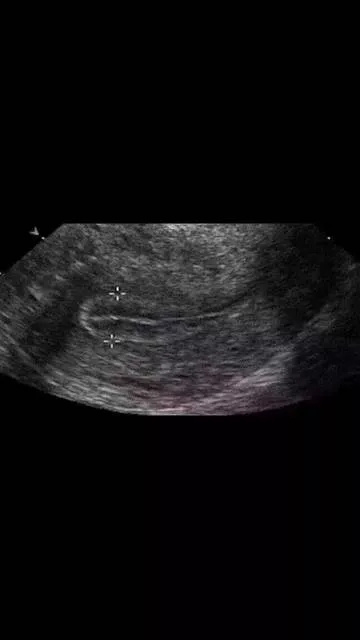

在平时进行内膜检测过程中,医生?;崴档侥谀ぬ?、太厚、不均质、有强光团,或内膜形态不好、三线不清、内膜线中断等等。

以上这些情况不利于胚胎着床和发育,不适宜移植新鲜胚胎,建议做一下宫腔镜检查,排除子宫内膜息肉、宫腔粘连、慢性子宫内膜炎症、内膜过度增生,以及双角子宫、单角子宫、子宫纵膈等等的病变,并进行相应的治疗。等内膜的病变去除,宫腔形态恢复以后再予以移植为好。